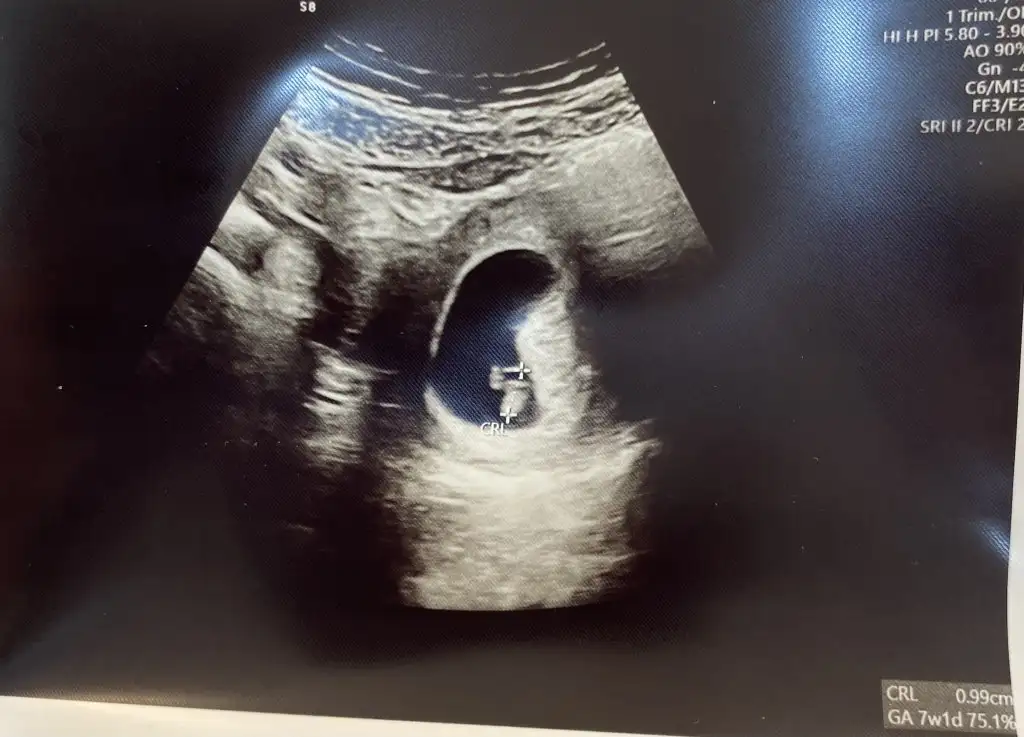

Kafam karıştı kızlar şimdi ilk attığım 5+2 vajinal ultrason, bugün ve şimdi yine attığım 7+1 karın ultrasonu tekrar bi bakıverin ayol ikisinde de aynı tarafta değil mi hiç anlamıyorum![]()

Kese: 5+2

Kalp atışı: 7+1

Tahmini doğum: 30.01.2024

Şehir: İstanbul

İlk çocuk.